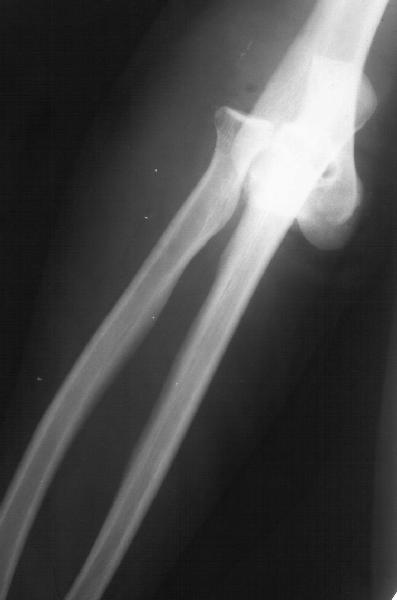

Пациентка 48 лет при падении с 5 этажа получила травму 28.04.02. Среди прочих повреждений был открытый задний вывих предплечья (см. снимок). Он был сразу вправлен, рана 6 см по внутренней поверхности

области локтевого сустава была обработана по месту первичного поступления. К нам поступила 7.05.02. Рана зажила первичным натяжением. Вчера, то есть через три недели после вправления, сняли повязку для разработки движений. Выявлено, что предплечье легко смещается медиально, и вправляется. Движения в локтевом суставе покаплохие. Свежие снимки и в правильном положении, и в подвывихе прилагаются. Вопрос - что делать? Продлить иммобилизацию гипсом? Идти на ревизию и восстановление внутренней боковой связки? Наложить шарнирный аппарат?Заранее спасибо.-- Best regards, Alexander N. Chelnokov